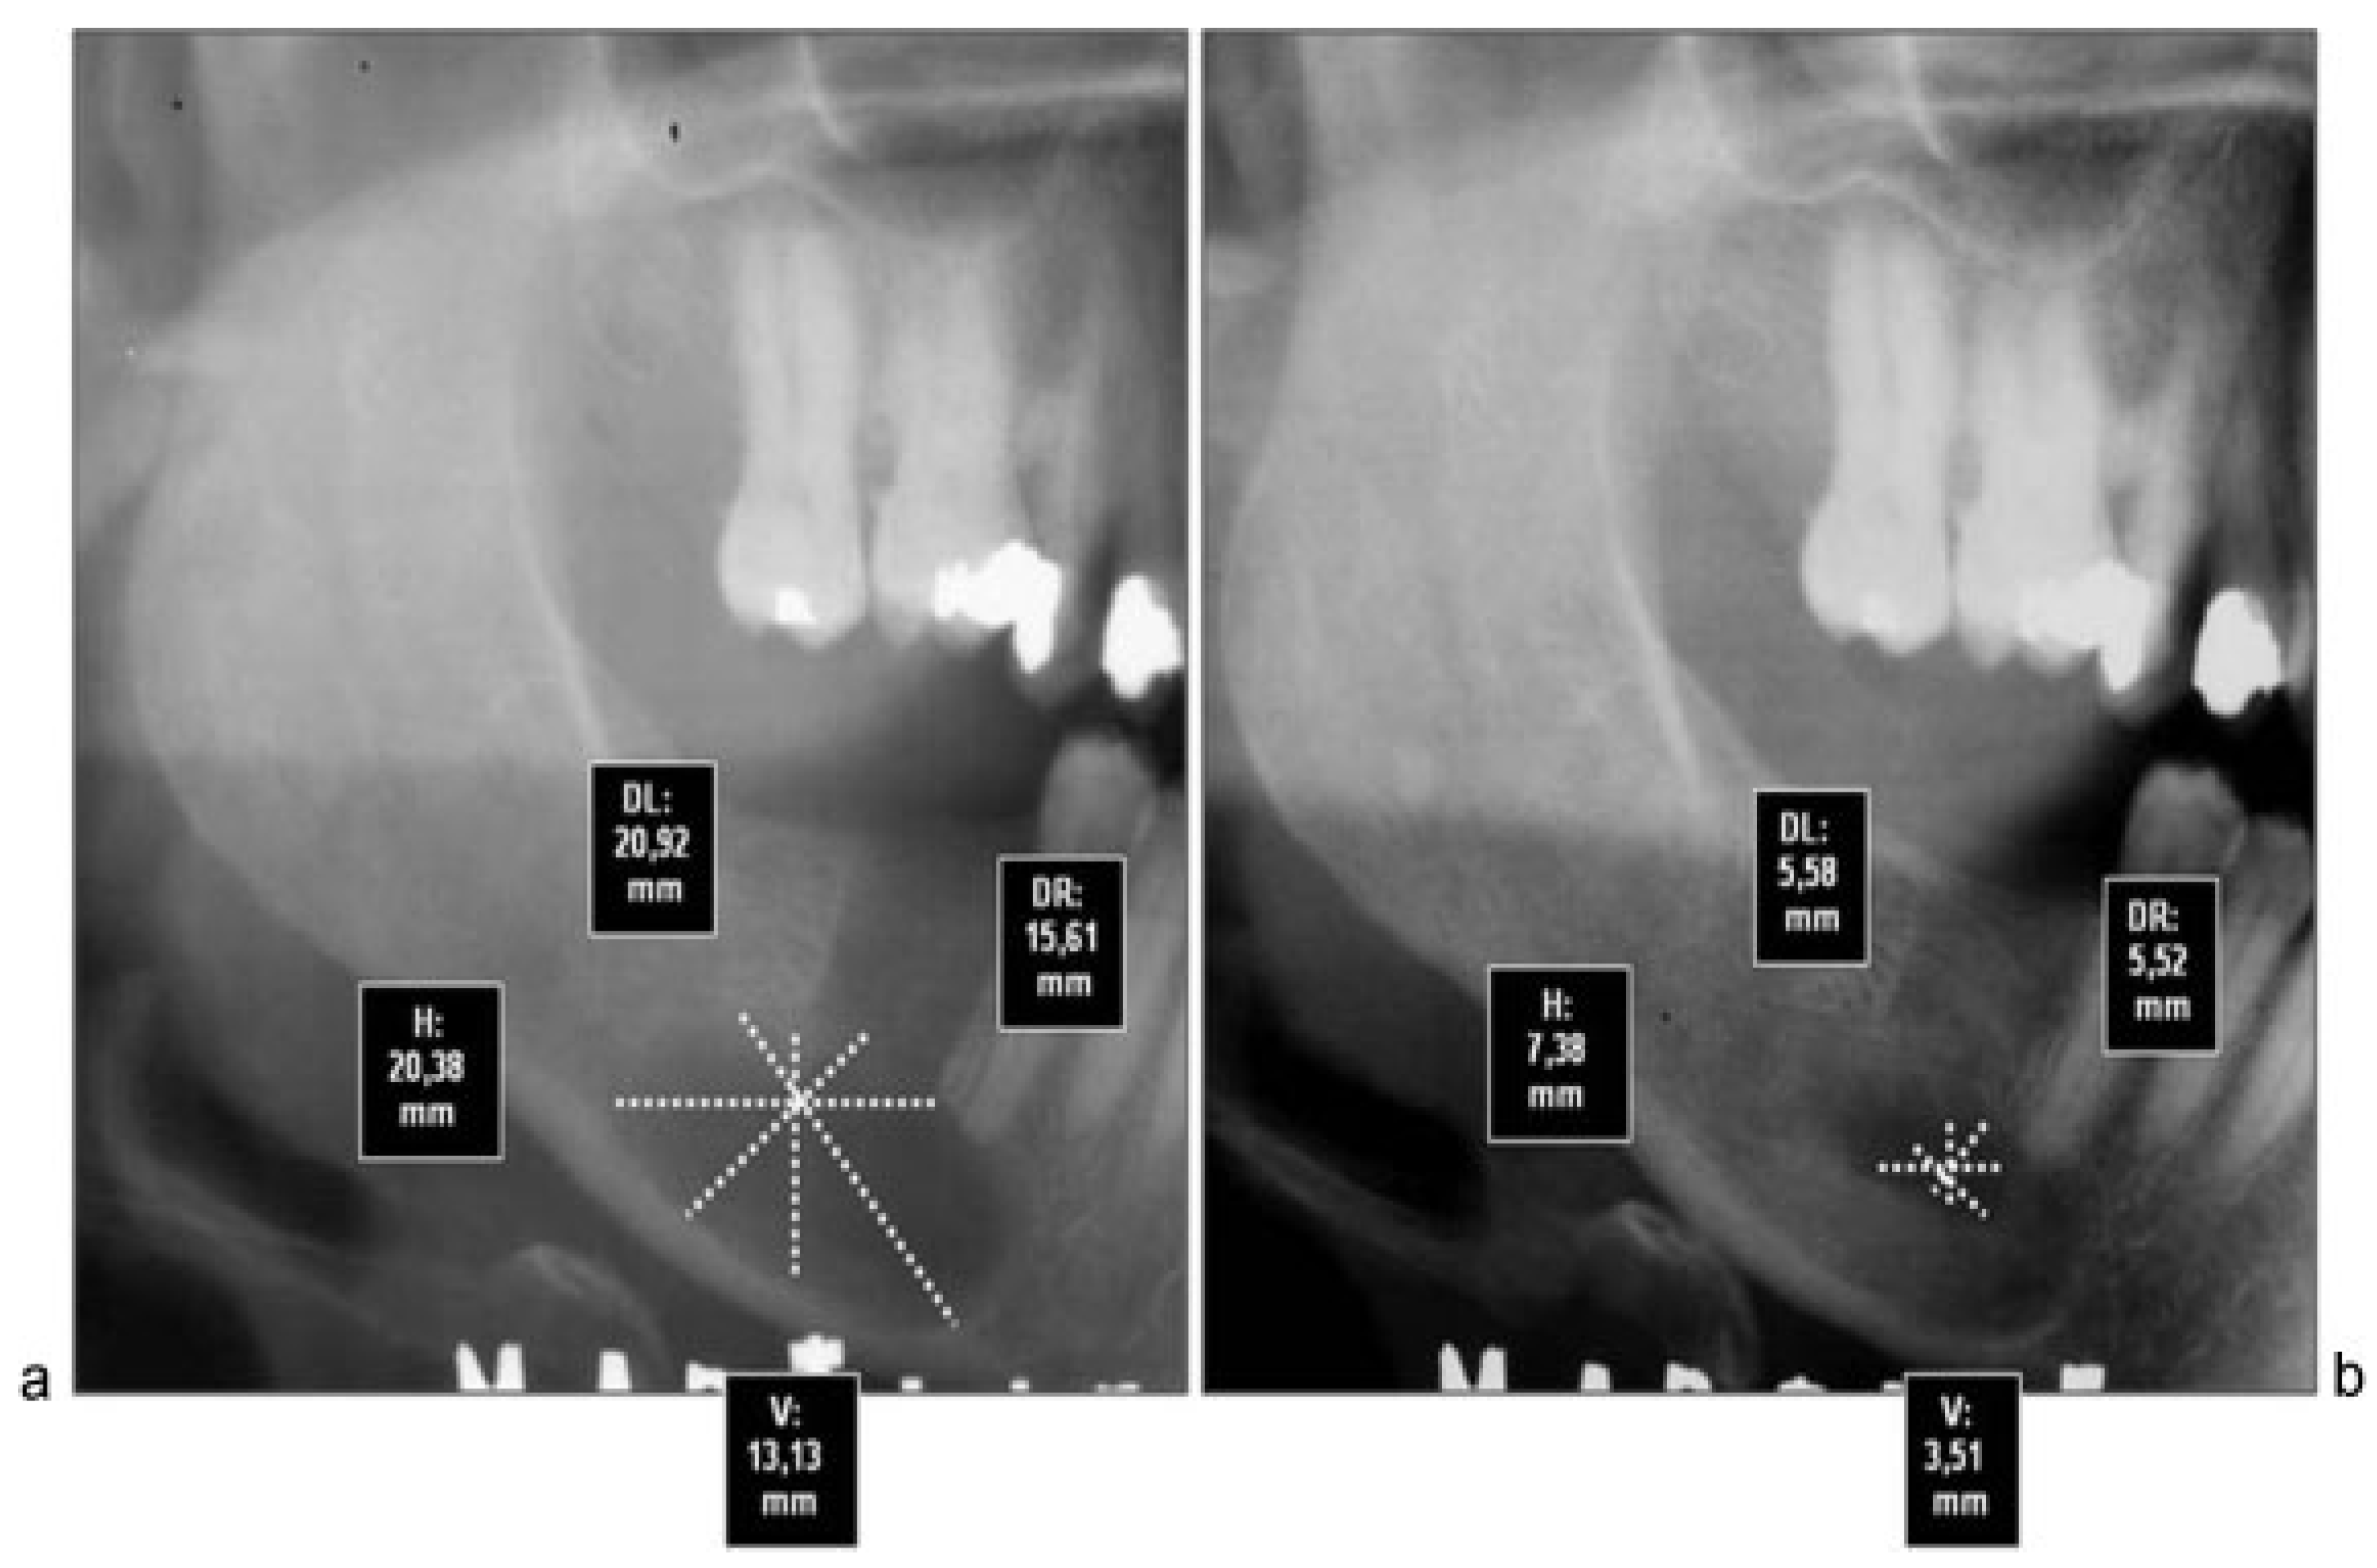

Although computed tomography provides better information about bone regeneration after surgery, to prevent high radiation dose panoramic radiographs can be considered enough for the purpose of postoperative control, so that we choose this last option (Figure 2a,b, Figure 3a,b and Figure 4a,b).

Figure 3. (a) Preoperative radiograph of patient 7 with linear measures after X-ray calibration with Nemoceph program. (b) Postoperative radiograph 12 months after surgery with total bone regeneration signs in residual cavity.